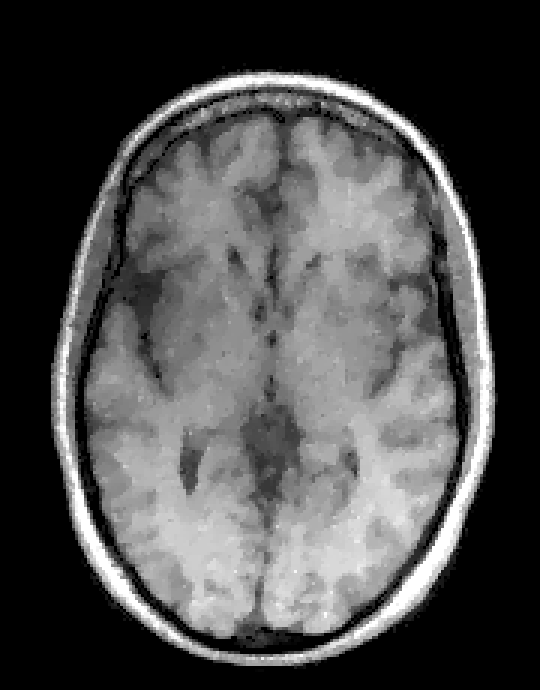

In the first set of evaluations, we considered the reconstruction of an MR image from -undersampled k-space data. The gold-standard magnitude and phase images, which were obtained from a real fully-sampled in vivo T1-weighted MRI acquisition with in-plane matrix size, are shown in Fig. 1. This figure also shows the k-space sampling mask (corresponding to undersampling) that we used to simulate an accelerated acquisition.